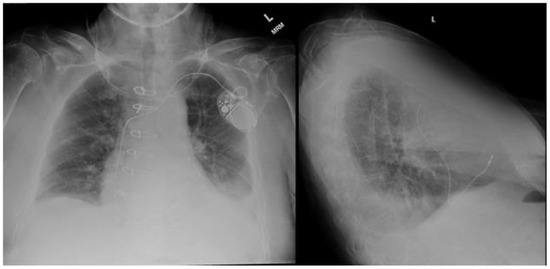

Standard posteroanterior and lateral chest radiography is often the initial modality employed to detect pleural effusion. On posteroanterior films, effusions are appreciated when the volume approaches 200 mL. Conversely, lateral views can visualize volumes as low as 50 mL [6]. In the intensive care setting, anteroposterior X-ray imaging is common, usually with the patient in a supine position. This positioning can cause pleural fluid to accumulate in the posterior thorax, making it less conspicuous on anteroposterior chest radiographs. In an upright patient, a pleural effusion typically presents on a chest X-ray as a uniform opacity in the lower lung field with blunting of the affected costophrenic angle (Figure 1). This effusion may display an upper border which curves up laterally, a radiological illusion created by a partially aerated lung between the anterior and posterior fluid layers known as the Ellis curve or meniscus sign [6]. Notably, a mediastinal shift away from the effusion is crucial for distinguishing pleural effusions from atelectasis. Utilizing lateral decubitus positioning to assess the layering of fluid is the most sensitive approach for detecting pleural effusions on chest radiographs. This positioning is capable of detecting effusions as small as 50 mL [7]. While chest radiography proves valuable in identifying pleural effusions, computed tomography and thoracic ultrasound offer greater sensitivity and detailed characterization of pleural fluid.

Figure 1. Posteroanterior (PA) and lateral chest radiography demonstrating a left sided pleural effusion. Image courtesy of Abdelkader Mallouk, Radiopaedia.org, rID: 71570.